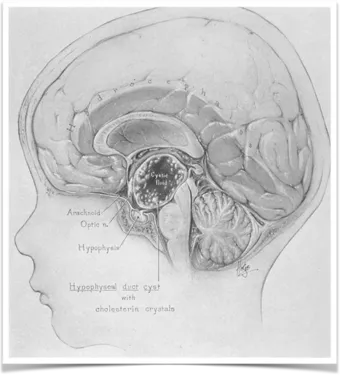

Walter E. Dandy在《脑外科手术》一书中对颅咽管瘤进行了图示说明。

颅咽管瘤起源于口咽粘膜的上皮残余组织。若将人体从头颈部划分为三个部分,可分别称为鼻咽、口咽和喉咽。颅咽管瘤的起源部位位于中间部分的口咽区域,其在妊娠第二个月就已开始形成并发育。原始鳞状粘膜内陷形成正中腺垂体和侧牙板束。

通过神经垂体和颊咽膜的融合过程,同时开始形成垂体和咽管结构。这两个结构在妊娠8周时相互融合,形成管状结构,并进一步演变为前漏斗。这些结构的粘膜成分残留,将导致沿下丘脑-咽管形成胚胎衍生物,最终发展为颅咽管瘤。